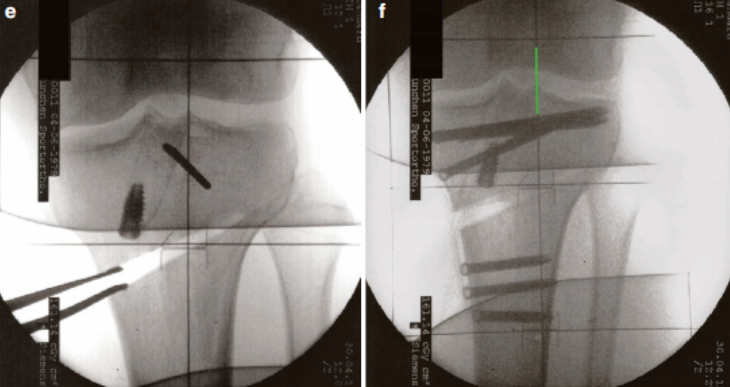

下图中我们可以一目了然地看到,当膝关节极度屈膝时,通过内侧入路观察,内侧辅助入路的导针能轻松地定位到股骨外侧髁内壁上前交叉韧带的解剖止点!

那是不是可以一个内侧入路就搞定呢?当然可以,建议在熟练后再进行,这个入路应该要兼顾标准的内侧入路和内侧辅助入路,两者取其中就可以,虽然会损失掉一部分股骨隧道的长度,但是整体来说是完全可行的,因为arth君就是这么干的!